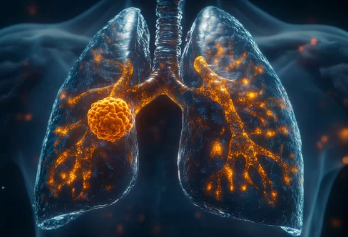

폐기흉(기흉, Pneumothorax)은 폐에 공기 주머니(기낭)가 터지거나 손상되면서 공기가 흉강(가슴막)으로 새어나와 폐가 수축하는 질환이다.

특히 젊고 마른 남성, 흡연자, 폐 질환이 있는 사람에게서 더 흔하게 발생할 수 있으며, 심한 경우 호흡 곤란 및 응급 상황이 발생할 수 있다.